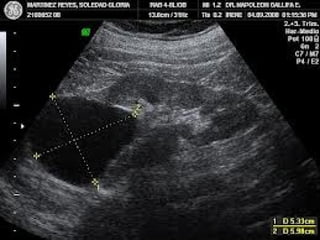

EVALUACIÓN ECOGRÁFICA

La evaluación de las glándulas adrenales

consiste en describir:

La posición,

La forma,

La ecogenicidad,

La arquitectura y

El tamaño de cada glándula adrenal.